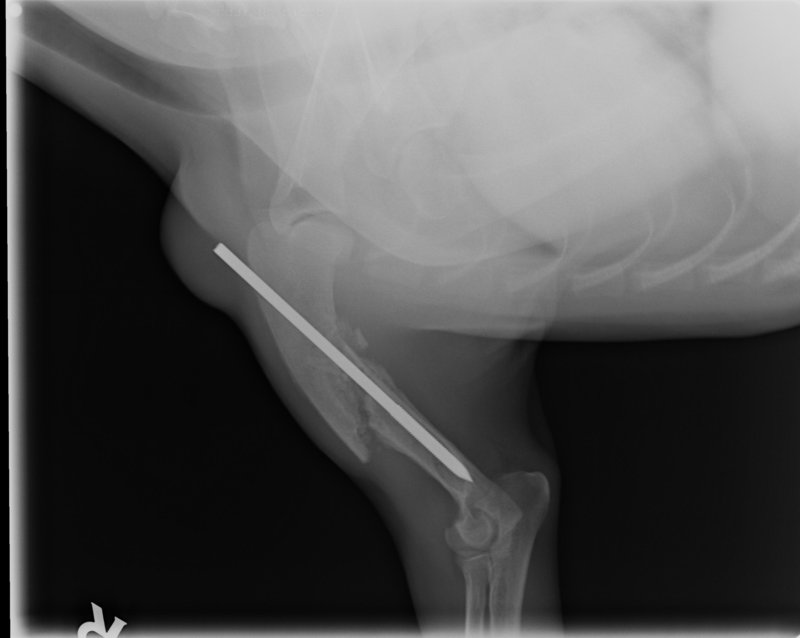

wir waren am 14. 12. beim Kontrollröntgen im Chir. Zentrum, und da hat man uns gleich mitgeteilt dass der Nagel den Benji im rechten Vorderbein hatte schon entfernt werden sollte. Haben ihn dann gleich rausnehmen lassen, und nach einer Woche der Schonung kann er jetzt bedenkenlos herumtollen. Der Knochen ist wirklich wunderbar verheilt, sieht man schön auf den Röntgenbildern:

Hier bei der Operation ca. Anfang März:

Einige Wochen später bereits Kallusbildung....

....und am 14. Dez. kurz vor dem rausnehmen!